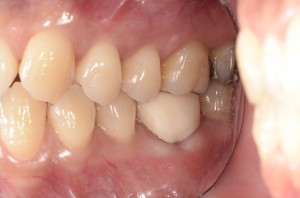

その後は、土台と仮歯を入れて経過観察させていただきました。

その後は、症状も特になく経過良好であることからかぶせ物を入れて終了となりました(^0^)/

終了時はこんな感じ!